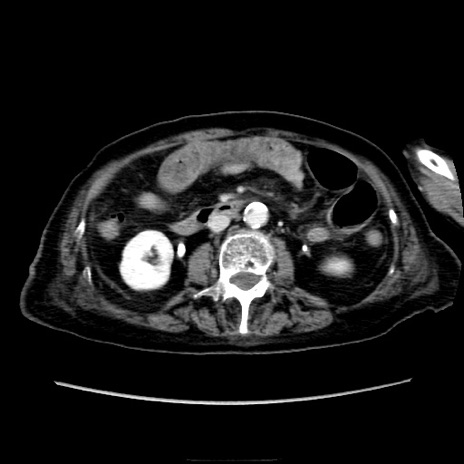

症例40(横断像)

【症例】90歳代女性

【主訴】腹痛・嘔吐

【現病歴】 食欲低下、嘔吐があり昨日他院受診。肺炎と診断され入院となる。入院後より腹部全体に圧痛あり。胃管留置され経過みていたが、症状持続するため、

当院転院となる。

【既往歴】胸椎圧迫骨折、胆石症

【身体所見】腹部:中央に激痛あり、圧痛あり、反跳痛不明

【データ】WBC 17100、CRP 18.82

横断像